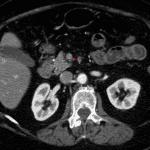

- Thrombus in the mid and distal SMA extending into proximal jejunal branches

- Mild luminal distension and wall hypoenhancement of an approximately 20 cm segment of jejunum in the left mid abdomen

- Acute mesenteric ischemia due to arterial occlusion

Thrombus in the mid and distal SMA extending into proximal jejunal branches which may represent in situ thrombus versus thromboembolism. Mild distension and wall hypoenhancement of an approximately 20 cm segment of jejunum in the left mid abdomen is concerning for developing bowel ischemia. No pneumatosis, portal venous gas, or pneumoperitoneum.